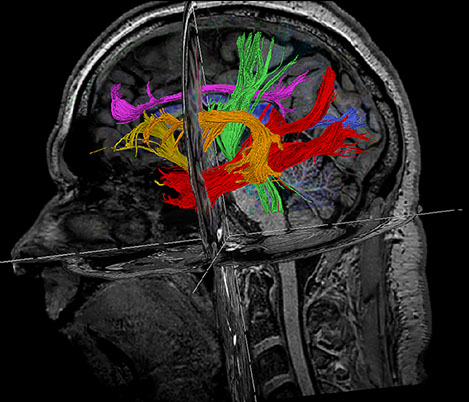

70% of radiologists consider neuro indications to be challenging, mostly due to a lack of appropriate imaging and visualization techniques¹. Philips aims to provide the best possible diagnostic clarity and treatment guidance for all patients with neurological disorders.

By leveraging our dStream digital platform, this year, we are introducing, a set of novel imaging and visualization strategies. These may empower you to resolve complex neuro questions with more certainty, as well as unlock new neuro territories in advanced Neurofunctional applications. This is a key step towards elevating neuro diagnostics and ultimately touching more lives with MR imaging.

New neuro applications

Take a look at our other neuro applications